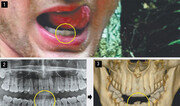

북한을 방문했다가 혼수상태로 풀려난 뒤 사망한 미국 대학생 오토 웜비어가 북한에 있을 때 고문을 당했을 가능성이 있어 보인다는 의사 소견이 나왔다. 그동안 북한은 ‘(웜비어가) 보툴리누스균에 의한 식중독에 걸려 치료 과정에서 수면제를 복용하고 혼수상태에 빠졌다’고 주장해 왔다. 24일 미국의소리(VOA) 방송에 따르면 웜비어를 진료했던 치과 의사들은 10일(현지 시간) 미국 연방법원에 제출한 진술서에서 “웜비어의 아랫니 2개 위치가 물리적 충격에 의해 변형됐다”며 폭력이나 고문 가능성을 제기했다. 웜비어의 부모는 4월 “웜비어가 북한의 고문으로 사망했다”고 주장하며 북한을 상대로 민사소송을 제기했다. 2014년부터 웜비어를 진료했던 치과 의사 타드 윌리엄스 박사는 웜비어가 북한에 가기 전에 찍었던 치아 엑스레이 사진과 웜비어 부검 당시 촬영한 두개골 사진을 진술서에 첨부했다. 두 사진을 비교해 보면 웜비어가 북한에 다녀온 이후 가운데 아랫니 2개의 위치가 주변 치아에 비해 뒤쪽으로 밀려난 사실이 확인된다. 2011년부터 2년간 웜비어의 치과 주치의였던 머리 도크 박사도 웜비어의 북한 여행을 전후로 그의 아랫니 중간 치아 4개의 위치가 크게 달라졌다는 소견을 밝혔다. 의식 불명 상태의 웜비어를 진료했던 대니얼 캔터 박사는 “보툴리누스균 중독 환자들이 일반적으로 보이는 증상이 웜비어에겐 나타나지 않았다”며 “웜비어의 사인은 뇌 손상으로 추정된다”는 의견을 내놨다. 토마스 오헤아 킨타나 유엔 북한인권특별보고관은 23일 뉴욕 유엔본부에서 열린 기자회견에서 북한 인권 문제 개선을 촉구했다. 킨타나 보고관은 이날 기자회견장에 자물쇠를 들고 나와 “탈북 소년에게서 받은 자물쇠 하나를 가져왔다”며 “그 소년은 ‘이 자물쇠를 당신, 유엔에 주고 싶었던 건 당신이 이 (북한 인권의) 자물쇠를 열 열쇠를 갖고 있다고 믿기 때문이다’라고 말했다”고 전했다. 그는 “(한반도) 안보와 평화, 번영에 대한 진전에도 북한의 인권 상황은 달라진 게 없다”며 “남북 정상의 공동선언이나 북-미 정상의 싱가포르 공동성명 모두 인권 문제를 언급하지 않아 매우 우려스럽다”고 말했다. 이어 그는 “북한과의 회담에서 인권 문제를 제기할 필요가 있다”고 강조했다. 북한 노동신문은 23일 개인 논평을 통해 “북한 인권결의안을 만드는 과정에 적극 참여할 것이라느니, 기권하지 않을 것이라느니 하는 소리들이 남측에서 울려나오고 있는 것도 스쳐 지날 수 없다”며 “민족적 화해와 단합, 평화와 통일을 바라는 겨레의 지향에 맞게 제정신을 차리고 온당하게 처신해야 할 것”이라고 으름장을 놓았다.뉴욕=박용 특파원 parky@donga.com / 위은지 기자}